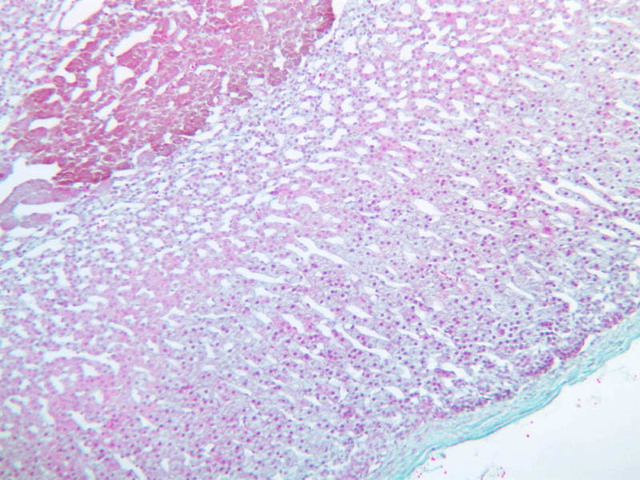

The adrenal gland (slide B-59, H&E [2.5x-labeled, 10x-labeled, 20x, 40x-labeled] [2.5x, 10x-labeled, 20x, 40x]; B-60, H&E [2.5x-labeled, 10x, 20x, 40x]; B-62, H&E [10x, 20x, 40x] [2.5x, 10x]) is a composite organ consisting of two functionally, structurally and embryologically different parts—an outer cortex and an inner medulla. Observe the gland at low power. Find the loosely organized tissue that comprises the medulla and the partially-separated columns of cells that make up the cortex. Scan the capsule and the tissue around it, looking for nerves and blood vessels. Study the pattern of cortical vasculature. In a pattern similar to that seen in the pars distalis of the pituitary, sinusoids run along the edges of columns or cords of cells. Owing to different arrangements of its constituent cells, the adrenal cortex has a layered appearance. From the capsule inward, these cortical layers are known as the zona glomerulosa, the zona fasciculata, and the zona reticularis.

The zona glomerulosa is located immediately beneath the capsule (B-60 adrenal gland, dog [10x, 20x] [20x, 40x]; B-59 [2.5x, 10x, 20x] [2.5x, 10x, 20x]). Its constituent cells are arranged in arcs or spheres, and, owing to their relatively small size, their nuclei appear to be close together. Cells of the zona glomerulosa secrete mineralocorticoids (e.g., aldosterone). The zona fasciculata consists of parallel columns or cords of cells that radiate toward the medulla and are separated by blood sinusoids (B-60 [2.5x, 10x, 20x, 40x]; B-62 [20x, 40x]). Owing to the extraction of lipids during histological processing, the cytoplasm of cells in the zona fasciculata appears highly vacuolated or "foamy". Cells of the zona fasciculata secrete glucocorticoids (e.g., hydrocortisone & cortisone) and some gonadocorticoids (weak androgens). The zona reticularis is the deepest cortical layer and lies adjacent to the medulla (B-60 [20x, 40x]; B-62 [20x, 40x]). It is characterized by irregular, interconnecting cords of cells which are separated by anastomosing capillary networks or sinusoids. Cells of the zona reticularis, which are smaller than those of zona fasciculata and do not contain as many lipid vacuoles, secrete gonadocorticoids and some glucocorticoids.